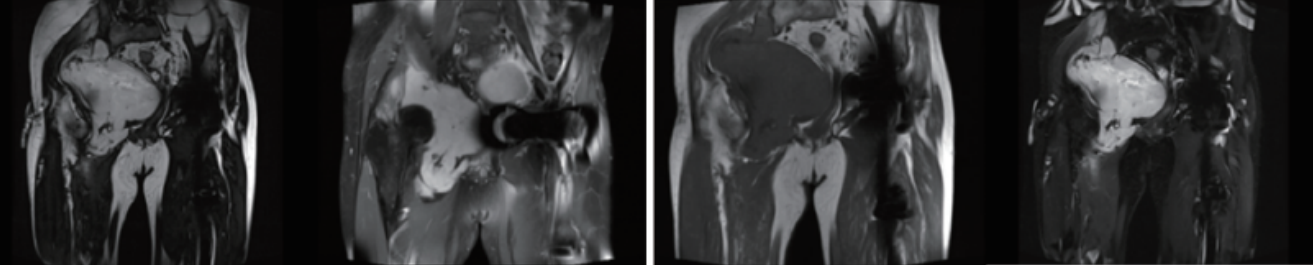

骨與軟組織腫瘤